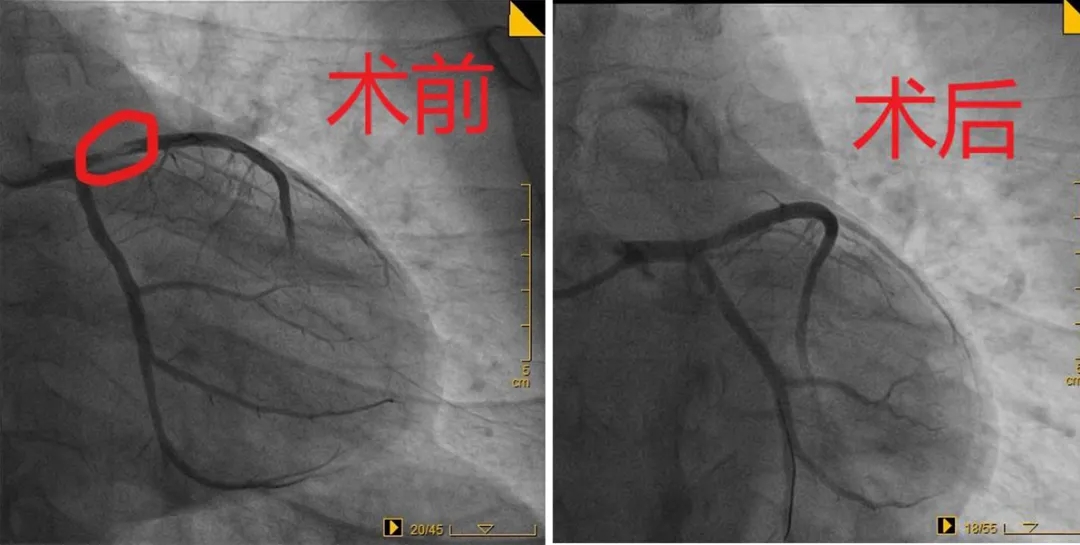

2020年12月14日,36岁的王先生因胸痛3天来我院就诊,诊断为急性冠脉综合症,急诊冠脉造影显示心脏左前降支近段狭窄80%。

该患者IVUS检查显示狭窄部位由斑块破裂引起,高希春主任、巩海英副主任为患者进行了冠状动脉药物球囊置入术。这样既解决了患者血管狭窄的问题,也没有放置金属支架,不需要长期服用抗凝药物,远期预后良好,患者非常满意。